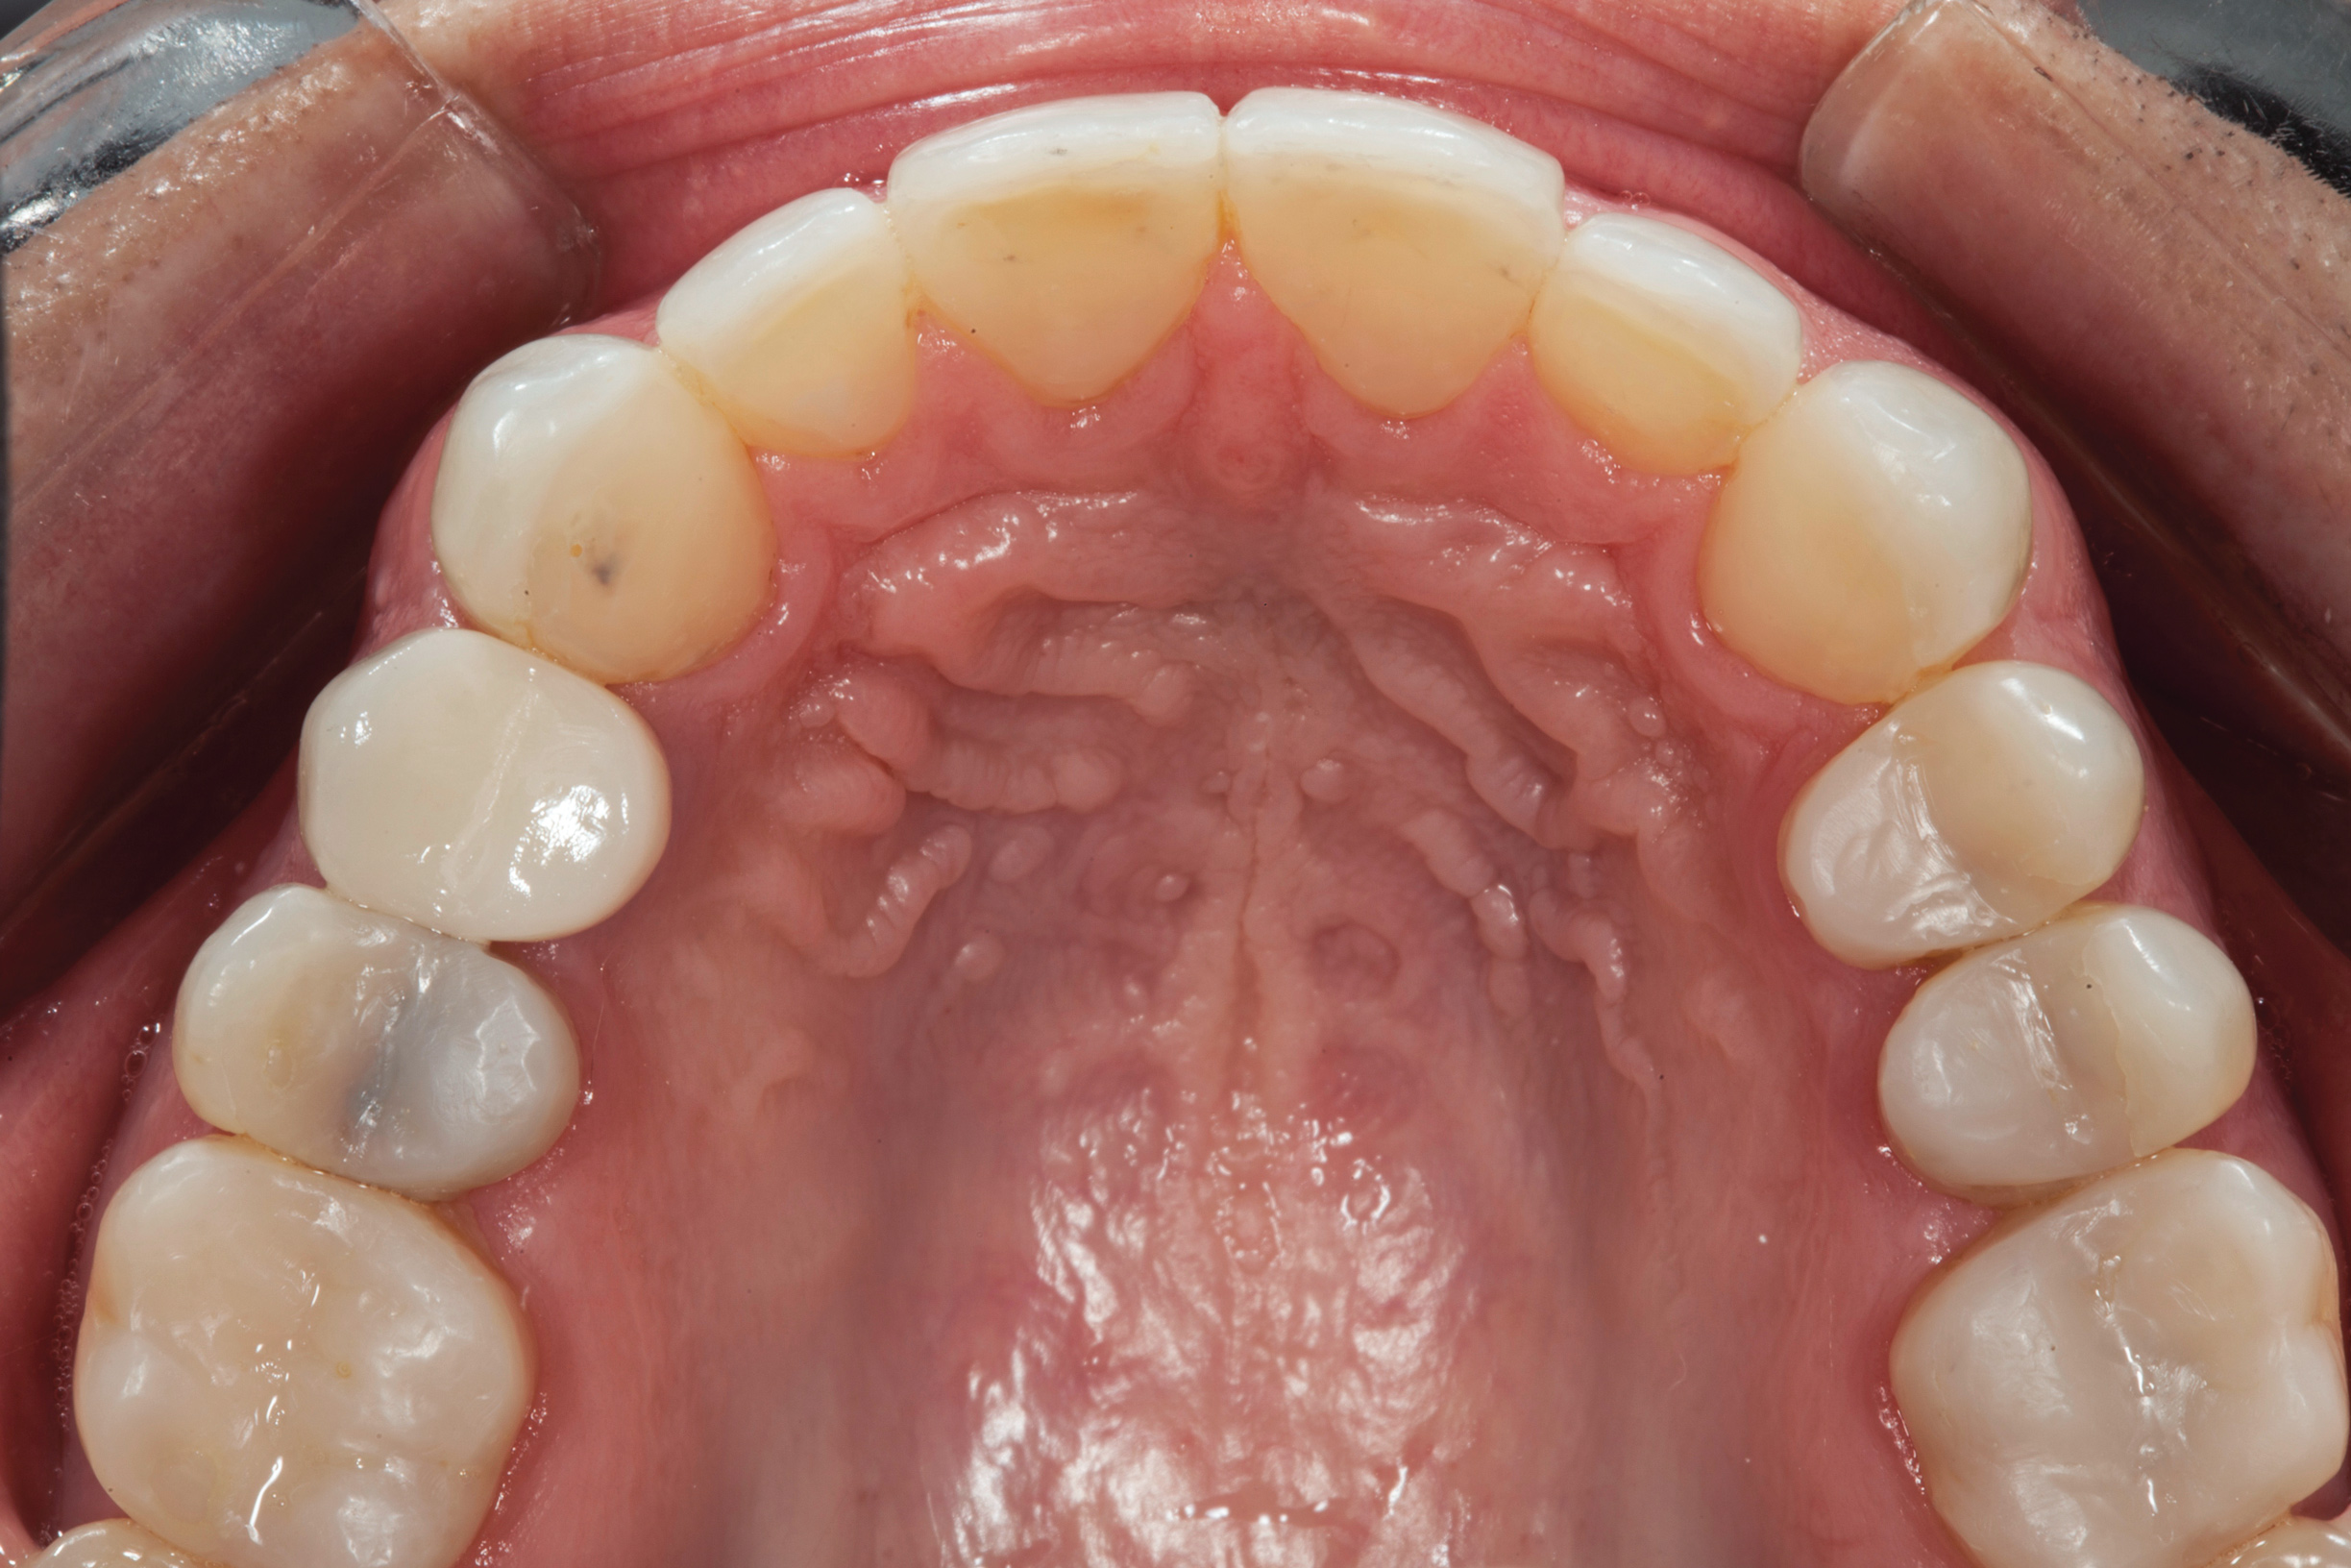

(4.) Preoperative occlusal view of upper arch.

Figure 4

A comprehensive examination was carried out, and preoperative photographs were taken (Figure 1 through Figure 4). The patient presented with fair oral hygiene and slight, generalized tissue inflammation. Caries and defective restorations were detected on teeth Nos. 4, 5, 13, and 14. The crown on tooth No. 12 was showing signs of leakage, and although the endodontic access cavity had been temporarily restored with composite, this endodontic re-treatment was acceptable and the tooth was otherwise symptom-free. Erosion was present on most of the posterior teeth and the cuspids, and abrasion was noted on teeth Nos. 4, 5, 10, 11, 20, 21, 22, 28, and 29. An examination of the patient's muscles, joints, and bite revealed no joint sounds, a normal range of motion, and negative joint load and immobilization tests.